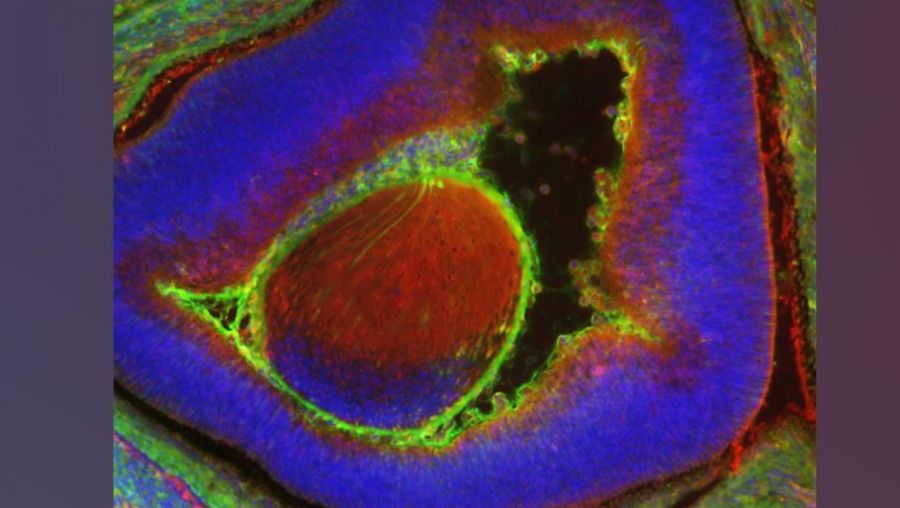

This figure shows a large quantity of human cells (labeled green) in a 17-day old mouse embryo (labeled blue). Most of the human cells are red blood cells, which are accumulated in the mouse fetal liver.

La imagen muestra una gran cantidad de células humanas (en verde) en un embrión de ratón de 17 días (en azul). La mayoría de las células humanas son glóbulos rojos, que están acumuladas en el hígado fetal del ratón.

En este estudio, el equipo de investigadores inyectó de 10 a 12 células madre humanas en embriones de ratones en desarrollo. En 17 días, esas células madre se convirtieron en millones de células maduras, incluidos los glóbulos rojos humanos y las células oculares.